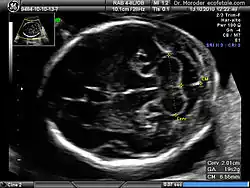

Ultrasound image of the fetal head at 19 weeks of pregnancy in a modified axial section, showing the normal fetal cerebellum and cisterna magna

Congenital malformation, hereditary disorders, and acquired conditions can affect cerebellar structure and, consequently, cerebellar function. Unless the causative condition is reversible, the only possible treatment is to help people live with their problems.[67] Visualization of the fetal cerebellum by ultrasound scan at 18 to 20 weeks of pregnancy can be used to screen for fetal neural tube defects with a sensitivity rate of up to 99%.[68]